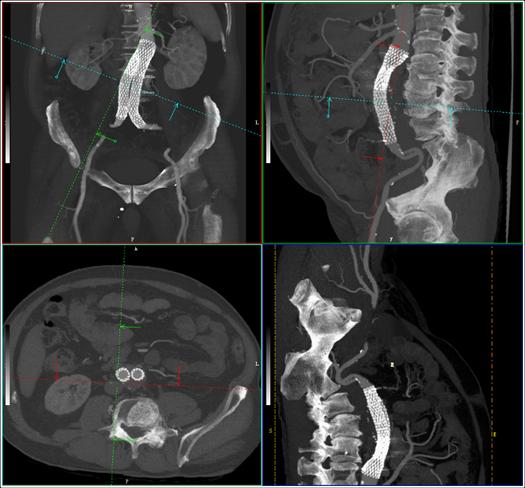

西安盈谷科技accuradpro 3d高级图像处理系统的增强功能,体数据下的组织分割功能,用于感兴趣区域血管自动/半自动交互提取。

多斜位mpr是完全基于容积数据处理(volume data processing,简称vdp)的处理方式,医生可以对容积扫描的数据在完整的体数据下,按照任意厚度、任意角度和任意曲面下,做平均值、最大/最小密度、容积重建、积分图像处理。